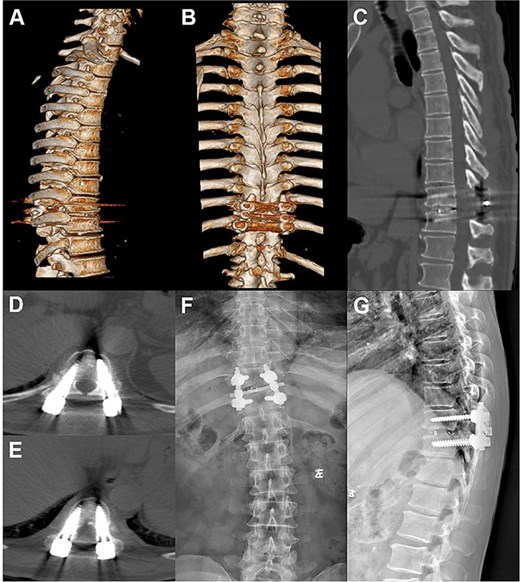

A 66-year-old male presented with a 1-year history of progressive low back pain and bilateral lower limb numbness, intensifying over the preceding month. Symptoms began insidiously without trauma and progressively worsened with prolonged standing and walking, improving with rest. The patient described deep, aching pain that significantly impacted his daily activities. Physical examination revealed bilateral lower limb numbness, especially prominent in the anterior thighs, an unsteady gait with a broad-based stance, decreased quadriceps muscle strength, reduced sensation below the navel extending to the groin, and positive bilateral Babinski signs indicating upper motor neuron involvement. Initial external X-rays suggested only L4 vertebral displacement, inconsistent with the clinical findings, prompting hospital admission for further evaluation. Refined imaging studies revealed previously unrecognized pathology. X-ray (Fig. 1A) and CT (Fig. 1B–D) demonstrated concomitant T10 vertebral body slippage, while MRI (Fig. 1E) showed severe T10/11 spinal cord compression with associated signal changes. The patient was diagnosed with thoracic spinal stenosis due to T10–T11 vertebral slip, explaining the bilateral lower extremity neurological symptoms and gait instability. Given the prolonged symptom duration, recurrent nature, and functional impact, surgical intervention was indicated after multidisciplinary discussion. The patient underwent T10–T11 thoracic interbody fusion with comprehensive decompression under general anesthesia. The procedure included herniated disc material removal, extensive posterior decompression, precise pedicle screw and titanium rod placement for stabilization, and autologous iliac crest bone grafting for interbody fusion. Postoperative management included comprehensive pain control and neurological monitoring. Follow-up X-ray (Fig. 2A and B) and CT (Fig. 2C–E) demonstrated successful vertebral realignment with the internal fixation in the ideal position. By postoperative Day 6, the patient reported significant back pain and leg numbness relief. Progressive improvement with structured physical therapy led to discharge on Day 10. One-year follow-up examination (Fig. 3) revealed stable fixation with continued symptom resolution, enabling free ambulation and complete return to normal activities.

Postoperative X-ray and CT showed that the slipped thoracic 10 vertebra was reset, the internal fixation device was ideally positioned, and the spinal cord compression had disappeared.

Postoperative follow-up images. (A–D) Repeat CT plain and 3D reconstruction at 6 months postoperatively showed ideal position of the T10–11 internal fixation and fusion device, straight posterior margin of the vertebral body, and no obvious signs of compression of the dural sac. (E, F) Review X-ray at 1 year postoperatively showed that the internal fixation device was in place without obvious dislocation, and the vertebral body slippage was satisfactorily repositioned.